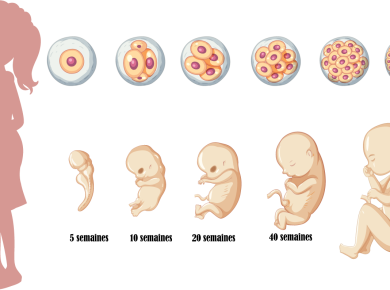

La grossesse est un moment unique dans la vie d’une femme, rempli de changements physiques et émotionnels passionnants. Les hormones jouent un rôle essentiel dans cette période de transformation. Dans cet article, nous allons explorer les changements hormonaux uniques de la grossesse, les effets sur l’exercice et l’activité physique, les rôles cruciaux de l’œstrogène et de la progestérone, et enfin, admirer les changements hormonaux de la grossesse.

Les femmes enceintes subissent des changements hormonaux et physiologiques remarquables. Les taux d’œstrogène et de progestérone augmentent considérablement, influençant l’humeur et le bien-être général de la femme. Les hormones de grossesse ont également des effets sur la peau, les cheveux et les ongles, créant l’éclat de la grossesse tant apprécié. En outre, les changements hormonaux affectent la capacité du corps à se nourrir et à soutenir la croissance et le développement du bébé.

L’œstrogène et la progestérone sont les deux hormones principales de la grossesse. L’œstrogène favorise la croissance des canaux de lait dans les seins et améliore la vascularisation de l’utérus et du placenta, facilitant ainsi le développement du bébé. La progestérone est responsable de la transformation de l’utérus pour accueillir le fœtus et de la relaxation des muscles et des articulations pour permettre le passage du bébé lors de l’accouchement. Sans ces hormones, la grossesse ne serait pas possible.

Les changements hormonaux de la grossesse ne sont pas seulement des inconvénients. Ils sont une preuve d’amour envers le bébé en croissance. Les femmes enceintes devraient être fières des changements qu’elles subissent et admirer les merveilles de leur corps en plein travail de développement. Les hormones de grossesse sont des éléments clés qui soutiennent la grossesse et assurent la naissance d’un enfant en bonne santé.